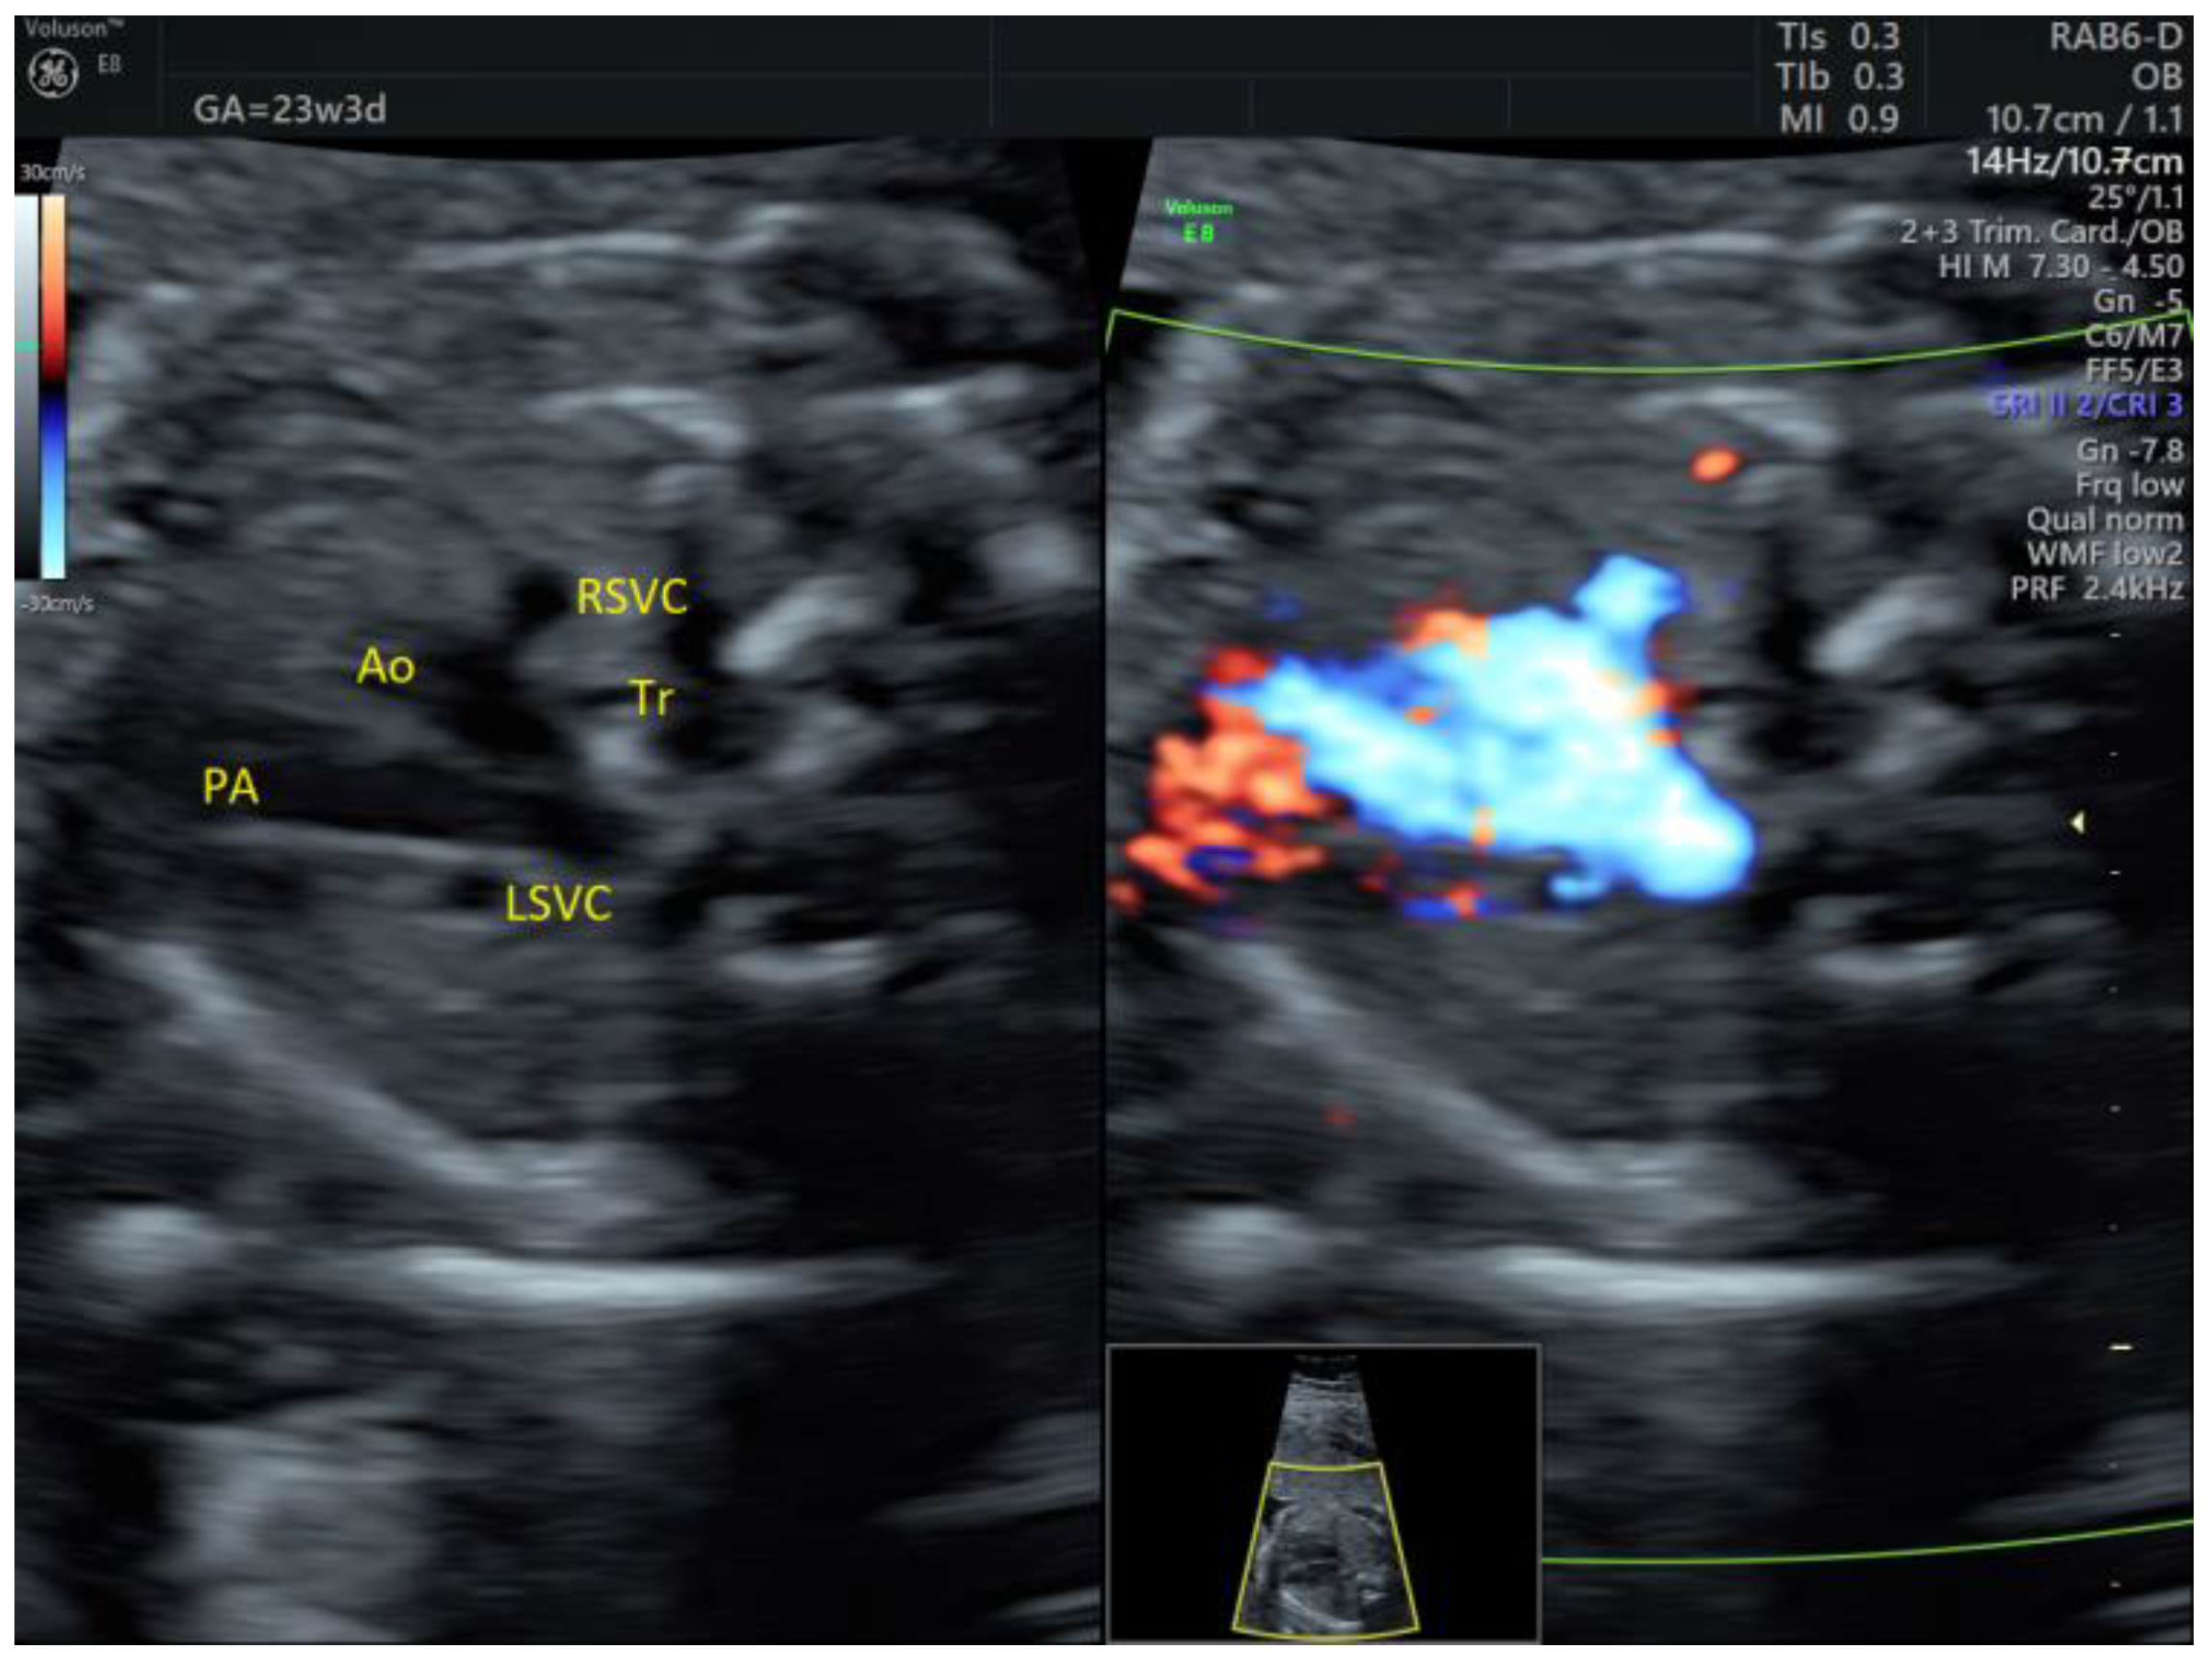

| PLSVC | 4 | - | - | 3VT color | + | 0 | 4 | 0 | 4/4 |